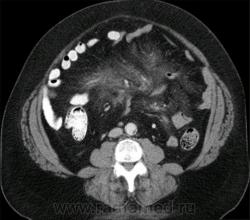

Иллюстрация 9.

Иллюстрация 10.

Иллюстрация 11.

9 - асцит?..

32 - поликистоз левой почки

32-мультикистоз